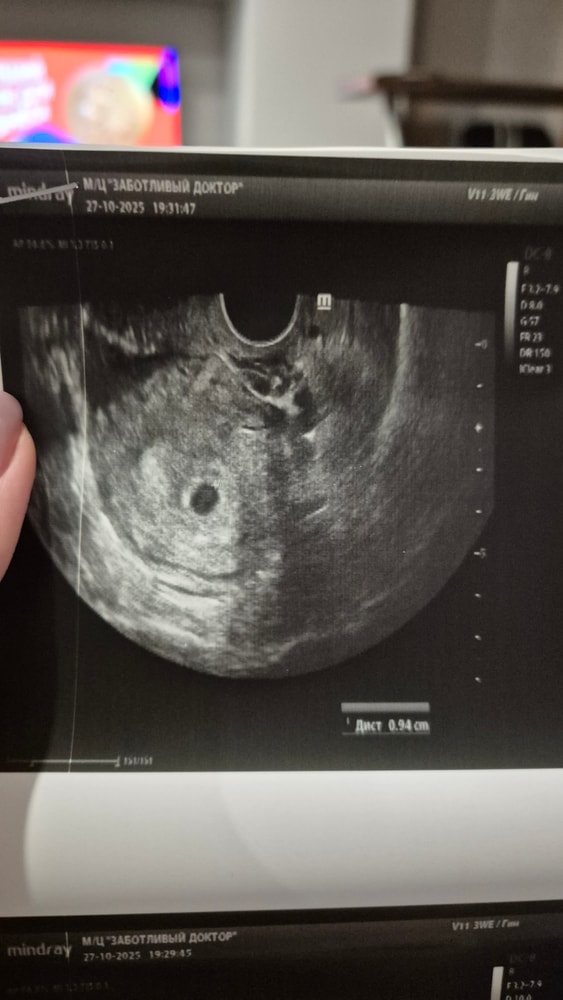

Изображение

Наталья , так тут же есть. Внутри пя видно колечко. Это врач вам сказал,что не видит???

Какой размер пя ?